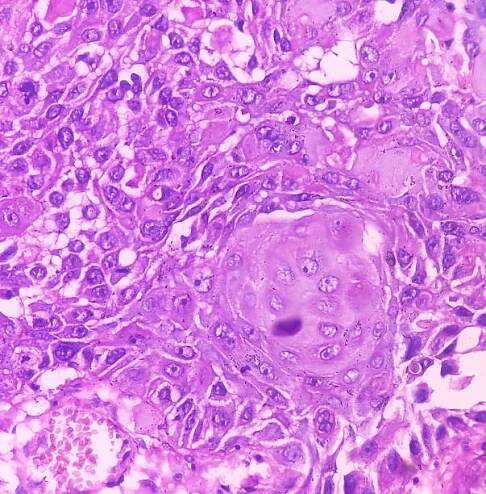

Skvamocelulární karcinom (latinsky Epithelioma spinocellulare) nebo také spinaliom je jedním z nejčastějších nádorů jak u lidí, tak u domácích zvířat. Jedná se o maligní nádor vytvořený z dlaždicovitých (spinocelulárních) buněk kůže. Tyto buňky jsou jednou z vrstev epitelové tkáně. Takové nádory se mohou vyskytovat také na sliznici. Wikipedie